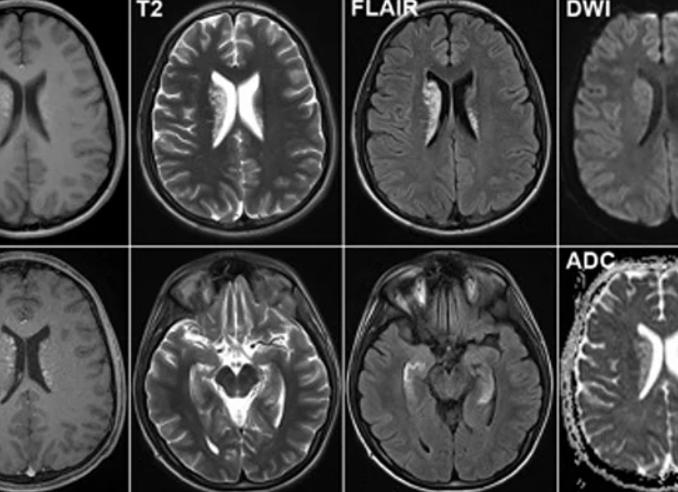

Вот так выглядит снимок с контрастом и без

Опухоль головного мозга. Слева без контраста, справа с контрастом.

Сравнительная разница МРТ без контраста и с контрастом